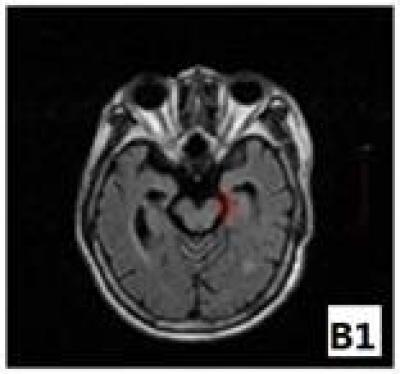

An MRI shows that the cerebral peduncle area on the affected side was shrunken at 6 months after cerebral infarction.

(Photo Credit: Neural Regeneration Research)